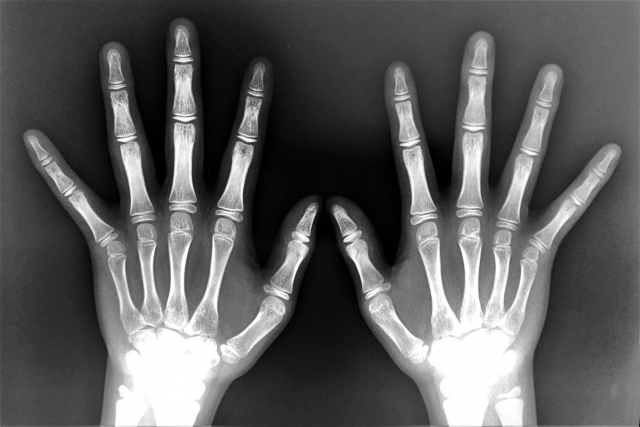

「これからどれくらい身長が伸びるのか知りたい」と思ったとき、正確に見極めるためには医療機関での検査が必要です。特に重要なのが「骨年齢(こつねんれい)」の測定です。これは、実年齢ではなく、骨の成熟度をもとに成長の余地を評価する方法で、将来どこまで身長が伸びる可能性があるかを知る手がかりになります。

骨年齢の測定には、手首のレントゲン撮影などが用いられます。この画像をもとに、骨端線の開き具合や骨の発達状態を確認し、成長の残り期間を判断するのです。また、ホルモンバランスや栄養状態を把握するために、血液検査が行われることもあります。